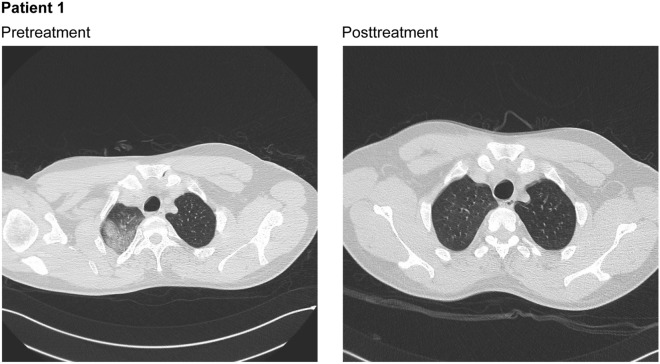

The patient was admitted to the hospital on July 8, 2020 (Table 2). Analysis of bronchial washing fluids confirmed the presence of SARS-CoV-2 (Table 2), and a chest computed tomography (CT) scan without contrast showed pseudonodular areas of parenchymal thickening in the right upper lobe with associated ground glass areas (involving 15–20% of the lung parenchyma) and some reactive mediastinal lymph nodes (Fig. 1). The patient was enrolled in the compassionate use study and treated with nebulized ribavirin from July 13 through July 19. On the third day of ribavirin therapy, a repeat nasopharyngeal swab, a conjunctival sample, and a SARS-CoV-2 antibody test were performed, all of which were negative.

Fig. 1.

Chest computed tomography scans without contrast for patient 1 at pretreatment, showing pseudonodular areas of parenchymal thickening in the upper right lobe with associated ground glass areas and some reactive mediastinal lymph nodes, and posttreatment after 6 days of therapy with ribavirin solution for inhalation, showing resolution of the pseudonodular areas and minimal residual subpleural areas

One day after completion of the ribavirin aerosol treatment regimen, a chest CT scan showed resolution of pseudonodular areas previously described, with only minimal residual subpleural areas of parenchymal thickening (less than 5% of the lung parenchyma; Fig. 1). On the same day, a nasopharyngeal swab tested negative for SARS-CoV-2. The patient was discharged on July 22 (approximately 3 days after completing ribavirin treatment) and returned to quarantine. At the end of quarantine, two sequential nasopharyngeal swabs for SARS-CoV-2 yielded negative results.